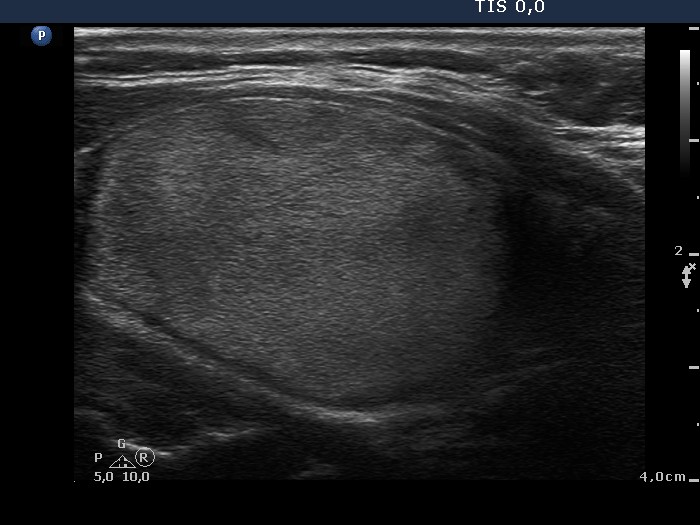

100 consecutive cases of papillary cancer - case 048 (ultrasonographic picture 5)

Left lobe, longitudinal scan.